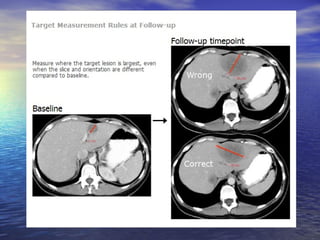

Baseline: 4,6 + 5,4= 10,0cm.

Follow-up: 3,3 + 2,7= 6,0 cm.

Decréscimo de 40% na soma das lesões= resposta parcial.